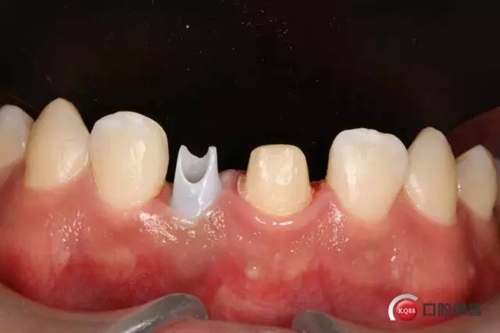

種植后修復(fù),我們要把握每一個(gè)細(xì)節(jié),比色,轉(zhuǎn)移桿的就位,我們必須把臨床做好,技工師傅才會(huì)給我們做出好的修復(fù)體,減少一些不必要的失誤,首先術(shù)前的檢查是必要一步 ,再是器械的準(zhǔn)備使我們臨床操作有條不紊,術(shù)前拍照,o-bite取咬合記錄,消毒修復(fù)術(shù)區(qū),旋出愈合基臺(tái),生理鹽水沖洗袖口,拍照袖口,安放合適轉(zhuǎn)移桿,拍X線見轉(zhuǎn)移桿就為良好,硅橡膠取模,術(shù)后旋回愈合基臺(tái),拍照比色。

藻酸鹽對(duì)頜取模,超硬石膏灌注。發(fā)加工廠,與技工溝通注意事項(xiàng),等修復(fù)體做好后,檢查模型。是否就位,是否密合,預(yù)約患者復(fù)診戴牙,消毒修復(fù)區(qū),旋出愈合基臺(tái),定位器指導(dǎo)安放修復(fù)基臺(tái),試戴冠,調(diào)磨鄰接及 咬合至合適,拋光,患者滿意,加力扳手加力至30N,拍X片見就位良好,特芙蓉及暫封膏封中央螺絲孔,聚羧酸鋅粘固劑粘固,或是樹脂水門汀粘固,清理多余粘結(jié)劑,光固化樹脂封螺絲孔,拋光。術(shù)后注意隨訪。